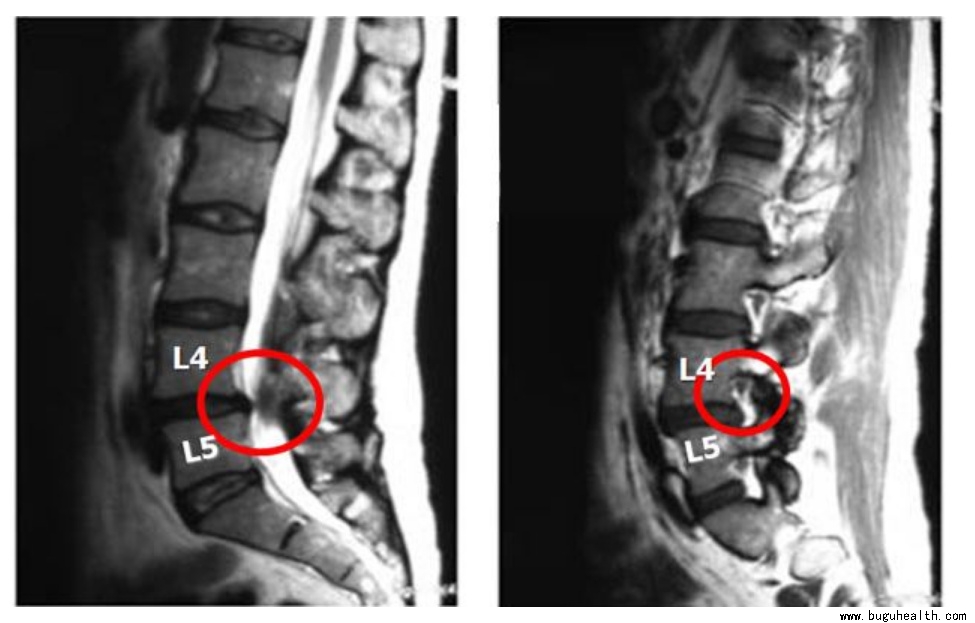

▼ 椎管狭窄典型症状:

1) 大多数腰椎管狭窄症患者,都有下腰痛的病史或伴有下腰痛。疼痛一般比较轻微,卧床休息则减轻或消失,腰前屈不受限制,后伸活动往往受限。

2) 马尾神经压迫症。腰椎管狭窄症可导致马尾神经受压迫,出现马鞍区的症状与体征以及括约肌的症状,严重时可出现大小便及性生活障碍症状。

3) 明显的腰腿痛症状和间歇性跛行

4) 检查脊椎偏斜不明显,腰椎正常,只是后伸痛。直腿抬高试验正常或只有中度牵拉痛。少数患者下肢肌肉萎缩,跟腱反射有时减弱或消失。

椎管狭窄的诊断要求详细的病史和体格检查,也可通过CTMRI判断,为判断神经功能障碍情况可能需要肌电图检查。